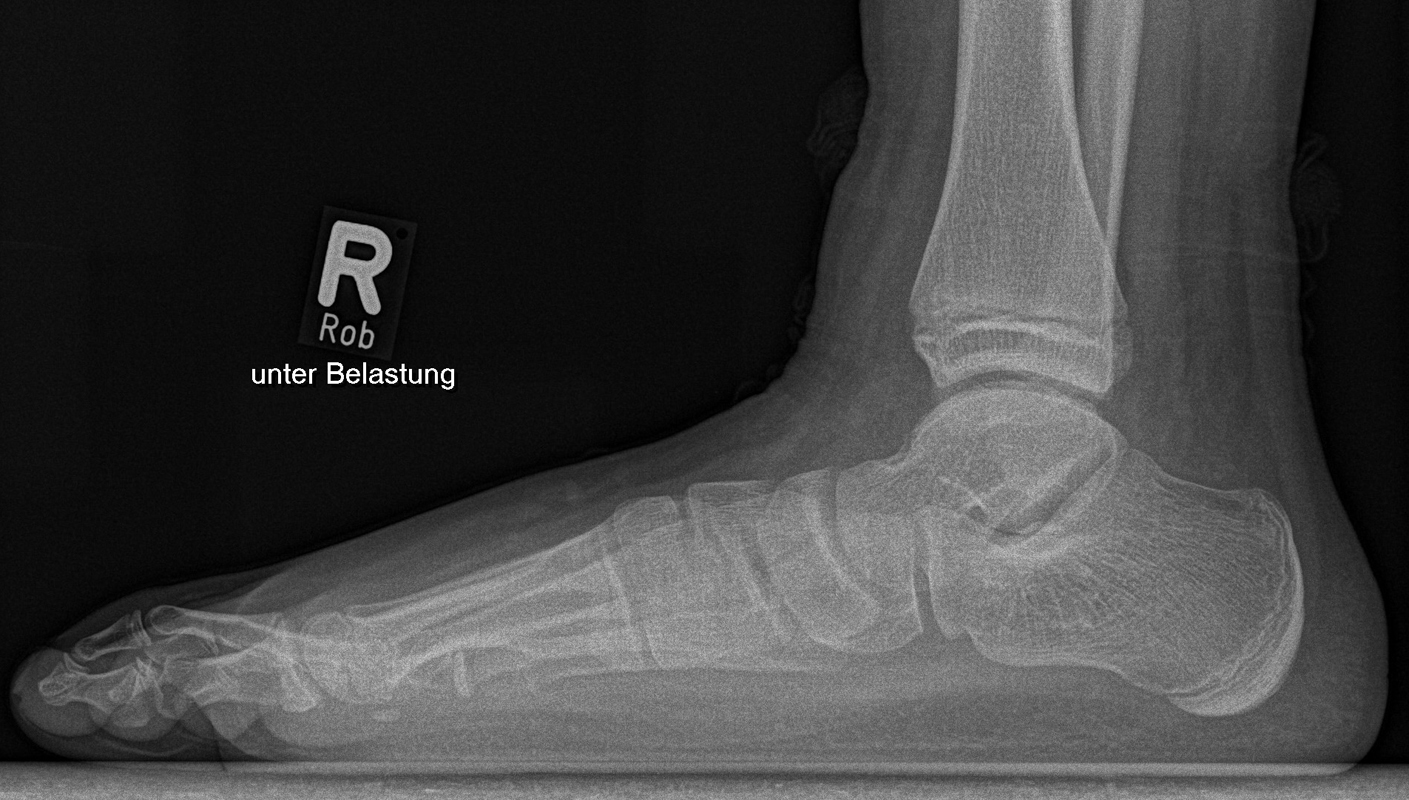

Knick-Senk-Platt-Fuß Korrektur mit dem Canalis Tarsi Spacer

In der Korrektur des schmerzhaften, aber flexiblen Knick-Senk-Fußes oder Plattfußes ist die Schraubenarthrorise mit einem Sinus tarsi oder besser bezeichnet als Canalis tarsi Spacer und alternativ mit einer Calcaneus-Stopp-Schraube seit vielen Jahren ein etabliertes Verfahren und führt zu einer kompletten Korrektur von flexiblen Knick- und Plattfuß-Fehlstellungen (Abb. 7). Die nötige Schnittlänge über dem Sinus tarsi beträgt für beide Verfahren 1 cm.